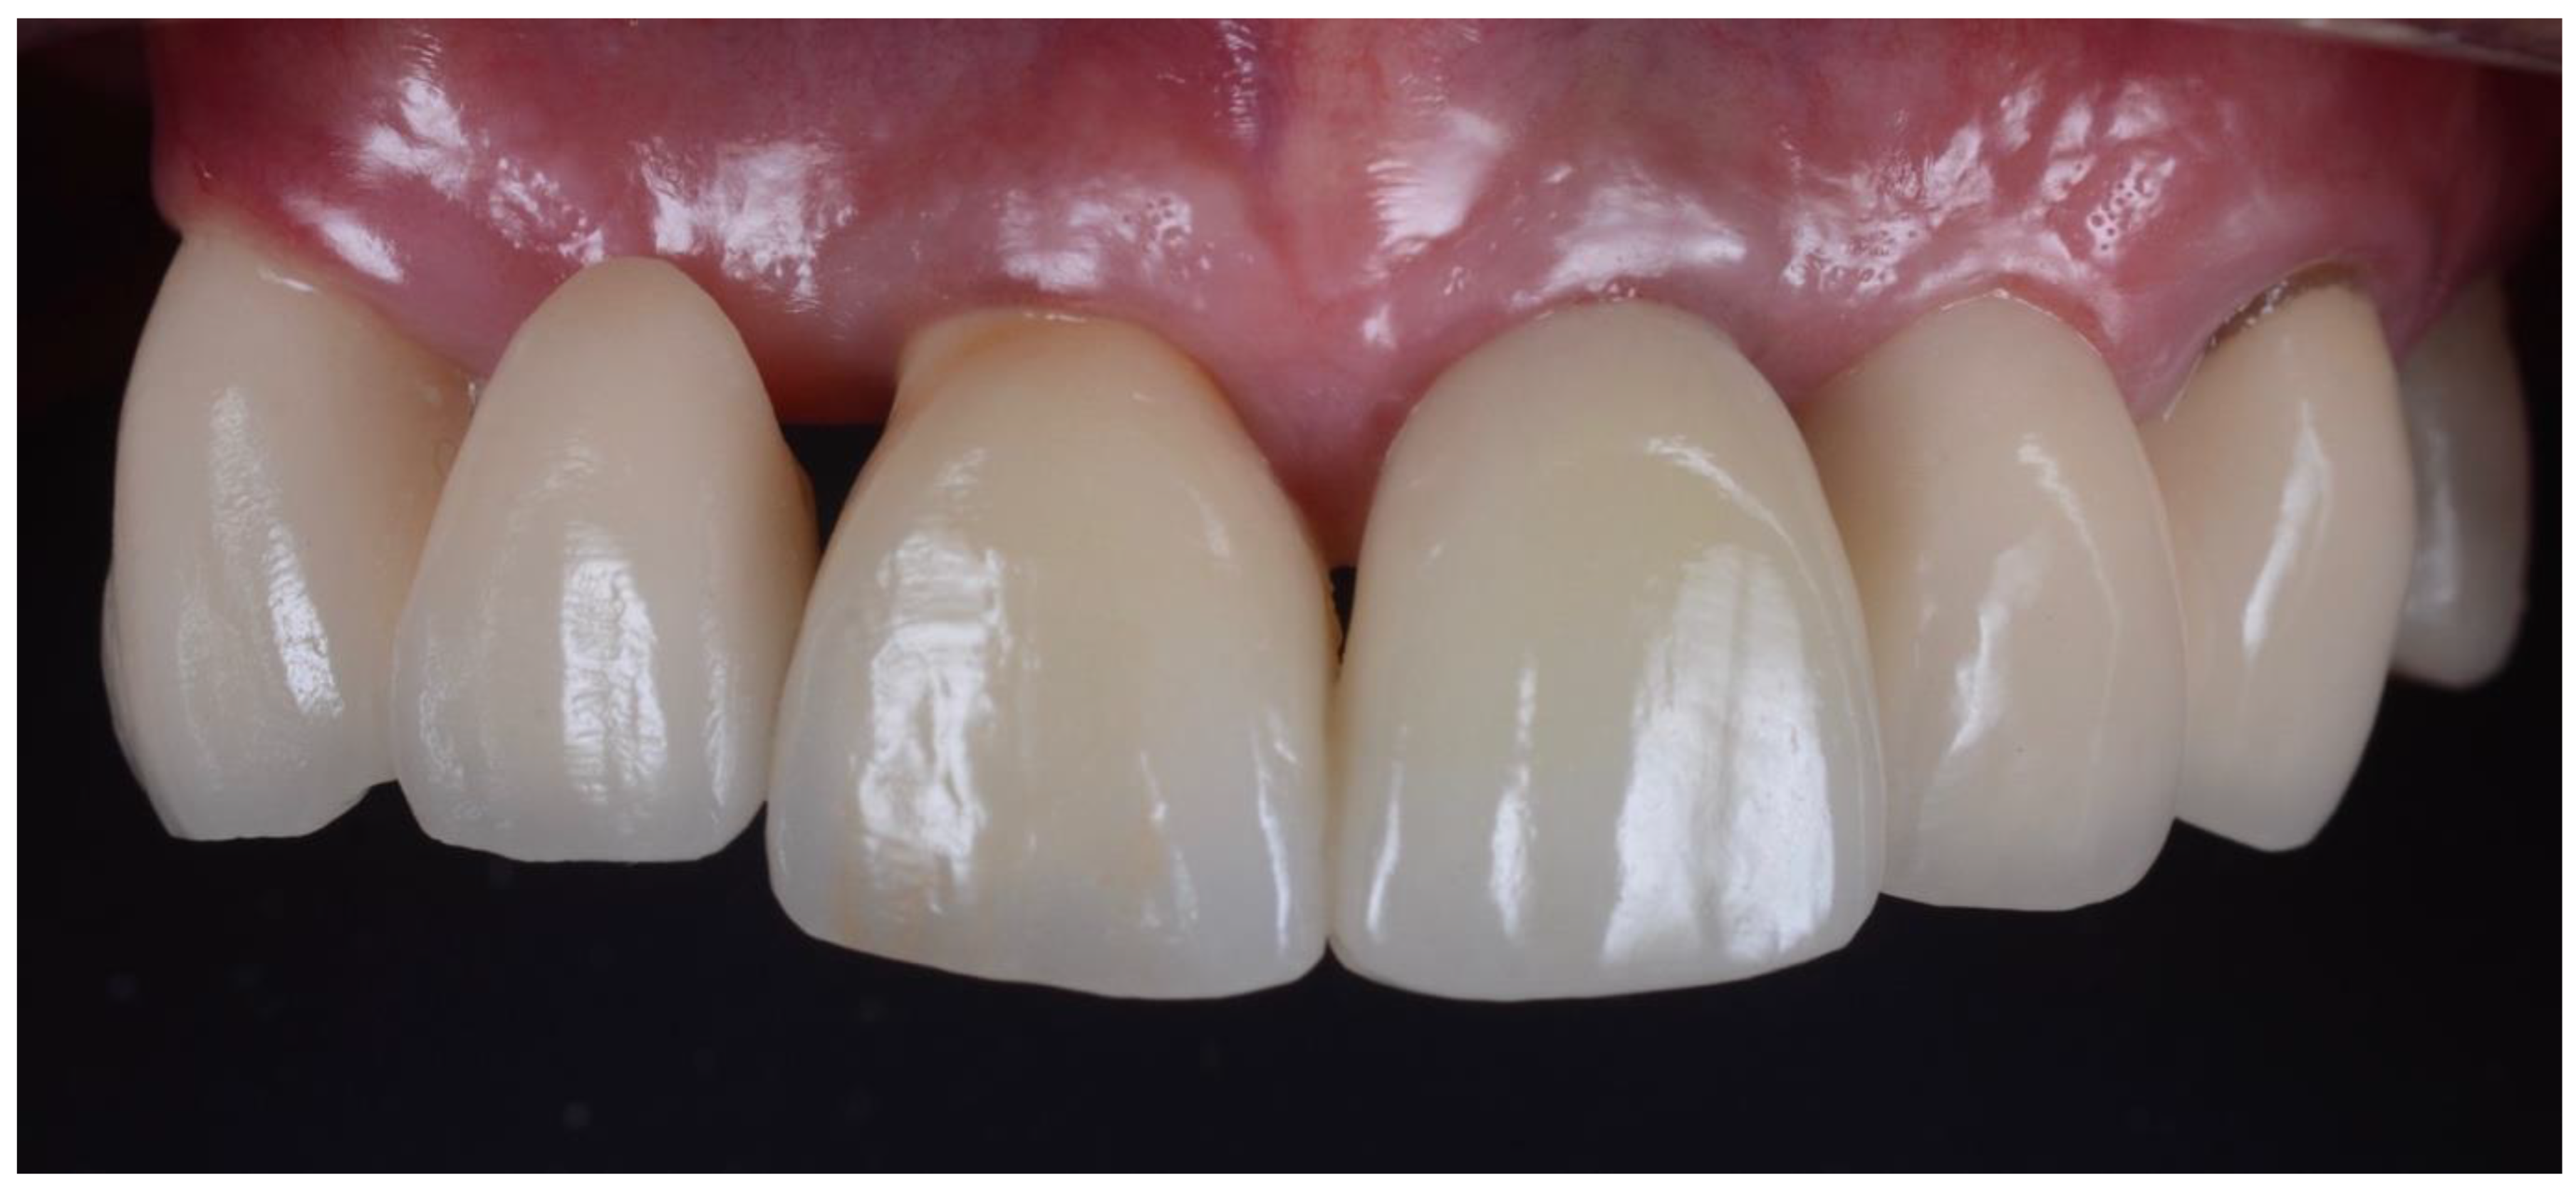

2.1. Surgical Technique